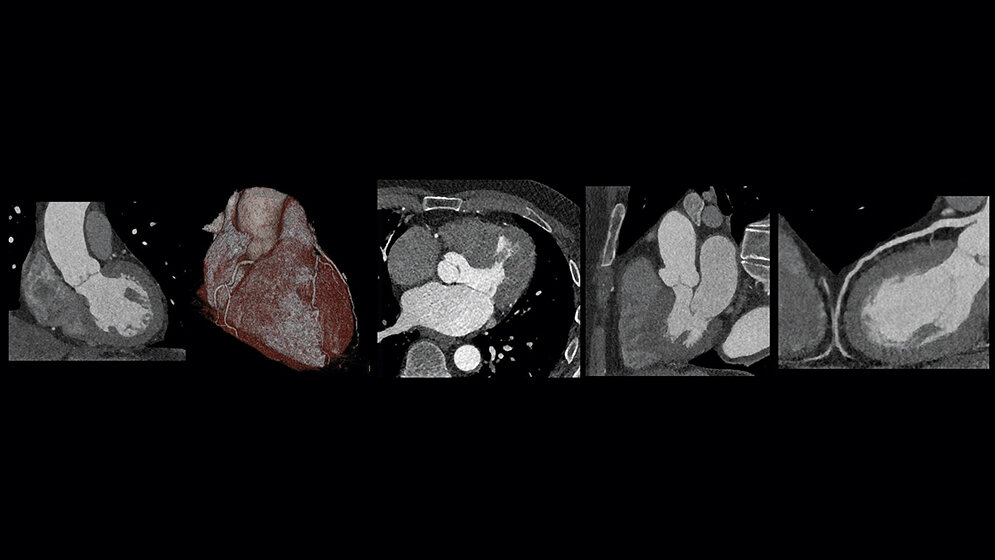

Die häufigste Fragestellung einer Computertomografie des Herzens ist die Darstellung der Koronararterien und der Ausschluss von Stenosen in diesem Bereich. Hierbei handelt es sich um Gefäße mit niedrigstem Durchmesser. Außerdem unterliegen sie zusätzlich der kontinuierlichen Bewegung des Herzens.

Hier beginnen auch schon die Anforderungen an unsere Computertomografen. Aufgrund der Darstellung kleinster Gefäße, benötigen wir eine hohe zeitliche wie auch eine hohe räumliche Auflösung. Einige CT-Geräte älterer Generationen können diesen Anforderungen allerdings nicht mehr gerecht werden, da ihre maximale zeitliche Auflösung ungenügend ist. Für die Darstellung der Herzkranzgefäße wird eine zeitliche Auflösung von circa 25 ms und kürzer benötigt. Dies bedeutet: Je besser die zeitliche Auflösung ist, desto geringer sind die Bewegungsartefakte und umso schärfer werden unsere Bilder. Ähnliches gilt auch für die benötigte hohe räumliche Auflösung. Diese ist elementar für die Abbildung kleinster Herzkranzgefäße.